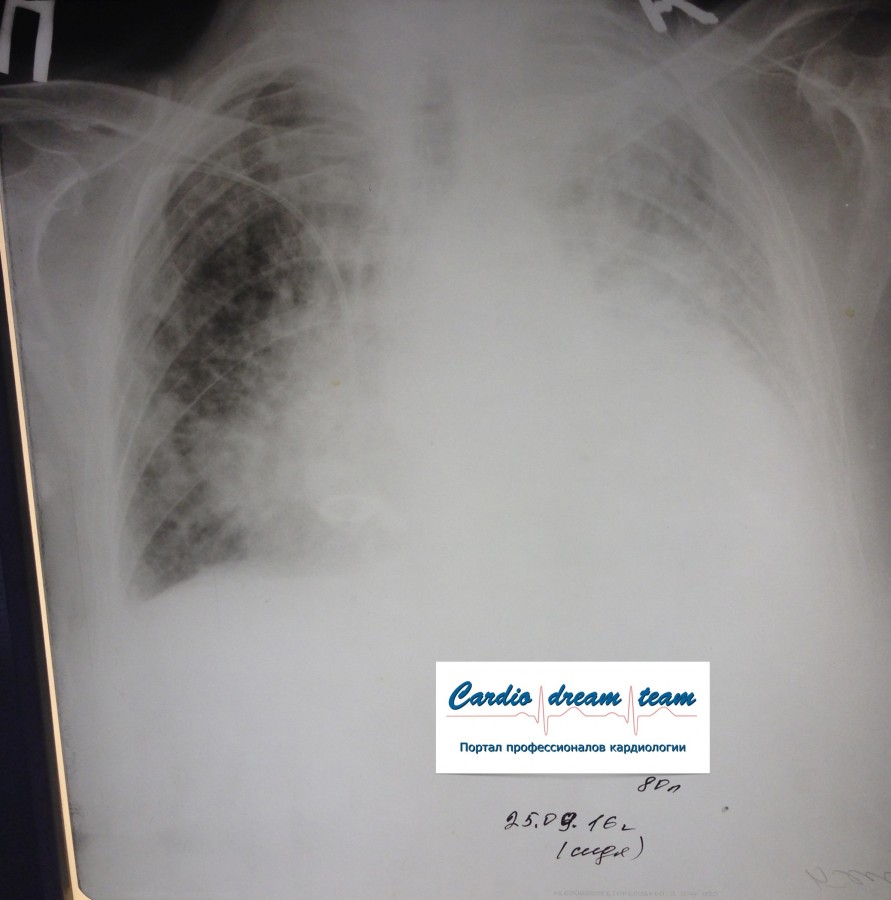

Центральный рак. Ателектаз слева.

Обсуждалось в Госпитале Ослабленных Сердец